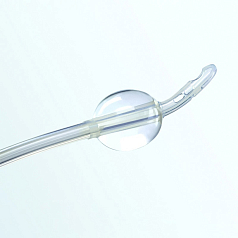

Трехходовые и двухходовые простатические катетеры используются в урологии после операций на предстательной железе.

Трехходовые и двухходовые простатические катетеры используются в урологии после операций на предстательной железе.